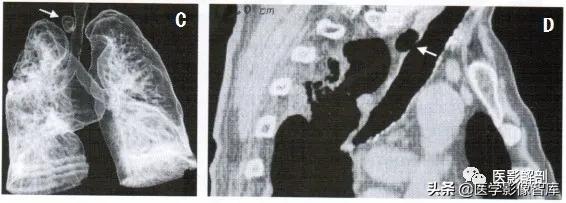

图1 气管憩室CT表现

A. CT平扫肺窗; B. CT平扫纵隔窗,气管右后方可见类圆形低密度影(箭),其内CT值与气 管内气体CT值一致; C. 支气管树最低密度重组图像,气管右侧的管状影(箭)与气管相连; D. 斜矢状面多平面重组图像,气管右后方可见类圆形低密度影,病变与气管壁相通(箭)。